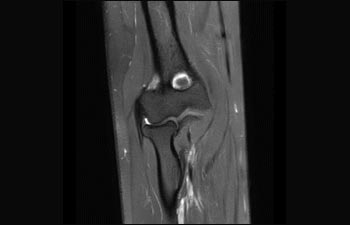

Find the right clinical applications for your needs

See all Ingenia Prodiva 1.5T coils